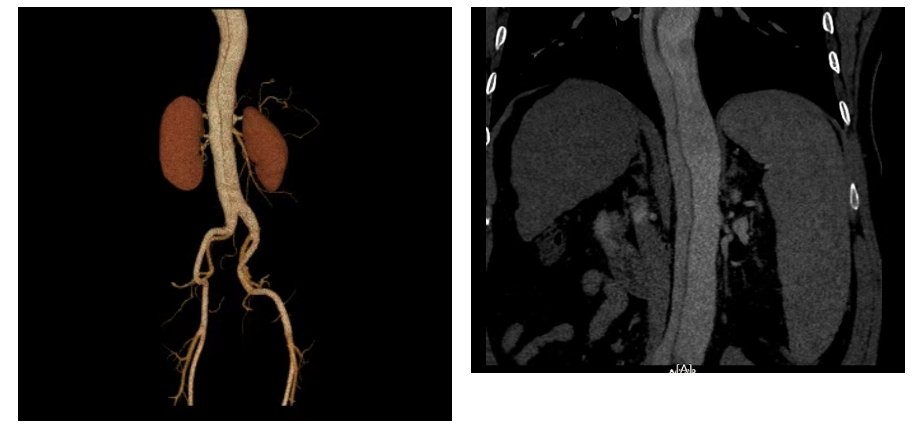

接到危急值报告后,临床医生迅速为患者安排了急诊主动脉CTA。CTA结果证实:患者确实有主动脉夹层,主动脉血管壁从内膜撕裂,血流冲入中层形成“假腔”,主动脉管腔呈“双腔”改变,后经完善主动脉CTA检查证实为Debakey III型。

诊断明确后,肝病中心联合心内科等相关科室专家紧急会诊,评估患者病情,为患者后续治疗赢得了极其宝贵的“黄金时间”。